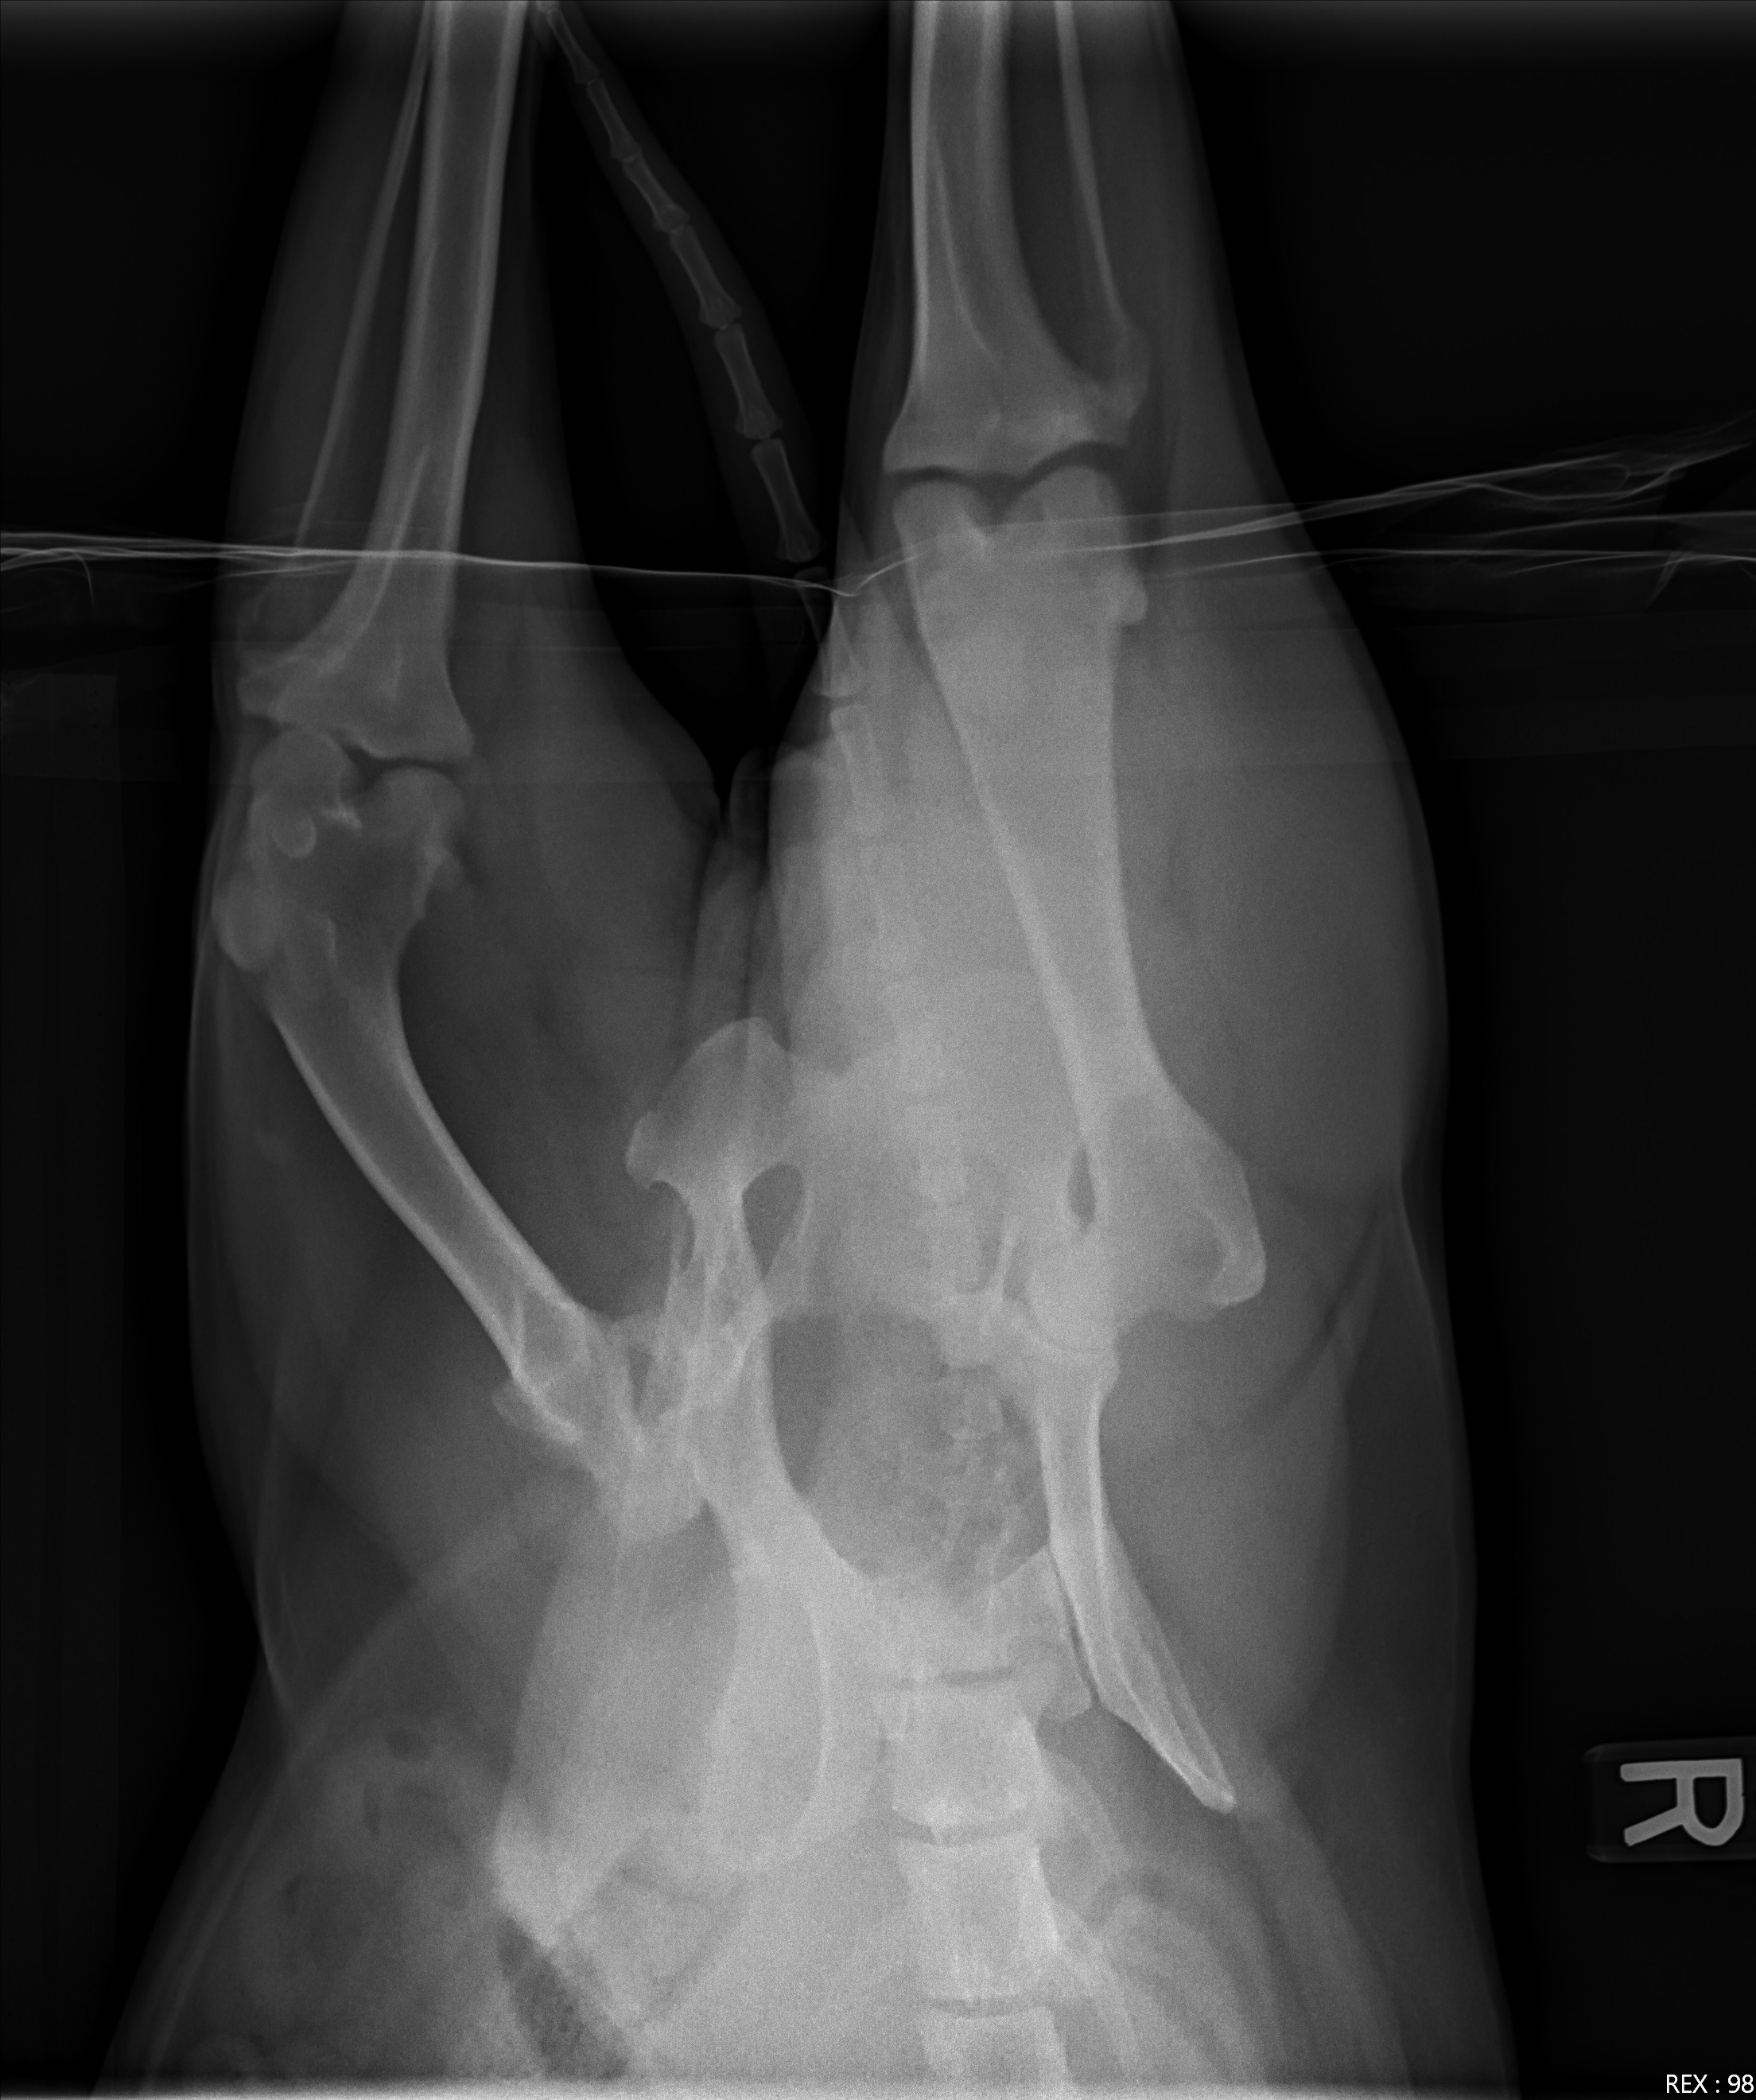

Hi everyone, I'm reaching out with a heavy heart to ask for your support for my beloved dog, Luke. He recently suffered a painful hip luxation and urgently needs a Femoral Head Ostectomy (FHO) surgery to relieve his pain and restore his mobility. Luke is the first dog we've ever had and he has infinitely brightened our days since we adopted when 6 years ago. Seeing him struggle has been heartbreaking. Any contribution, big or small, will help us get him the care he desperately needs. Thank you so much for your kindness and support.